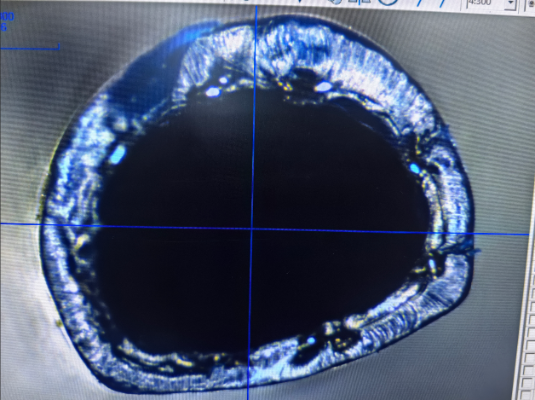

Profilowany cewnik pleciony to cewnik medyczny zaprojektowany z plecioną strukturą i specjalnie wyprofilowanym kształtem przekroju poprzecznego. Jest zwykle stosowany w procedurach medycznych wymagających dużych prędkości przepływu i stabilności. Godną uwagi cechą tego cewnika jest połączenie jego wewnętrznej i zewnętrznej ścianki z plecionymi materiałami, co poprawia transmisję płynu przy jednoczesnym zachowaniu elastyczności i trwałości.

„Wyprofilowany” aspekt tego cewnika polega na tym, że jego przekrój nie jest zwykłym okręgiem, ale raczej specjalnie zaprojektowanym kształtem, takim jak elipsa, wielokąt lub inna forma nieokrągła. Warstwa plecionki zwiększa wytrzymałość, dzięki czemu profilowany cewnik pleciony jest w stanie wytrzymać zarówno ciśnienie wewnętrzne, jak i zewnętrzne, zachowując swój kształt i funkcję nawet pod obciążeniem.